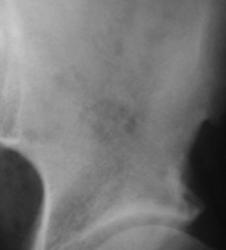

Согласна, надо Рейнберга почитать. Когда-то давно попадался остит в области лонного сочлениея. Это был пожилой мужчина после операции на простате. Процесс был отрый. Может быть в данном случае исход этого заболевания. Или перестройка связана с коксартрозом. Раз головка бедра деформиррвана, надо поискать асептический некроз.

Что можете коллега посоветовать по поводу лонного сочленения.

Даже не знаю, что это может быть. Со взрослыми не работаю. Где-то у Рейнберга встречала про склеротические изменения симфиза, завтра посмотрю.